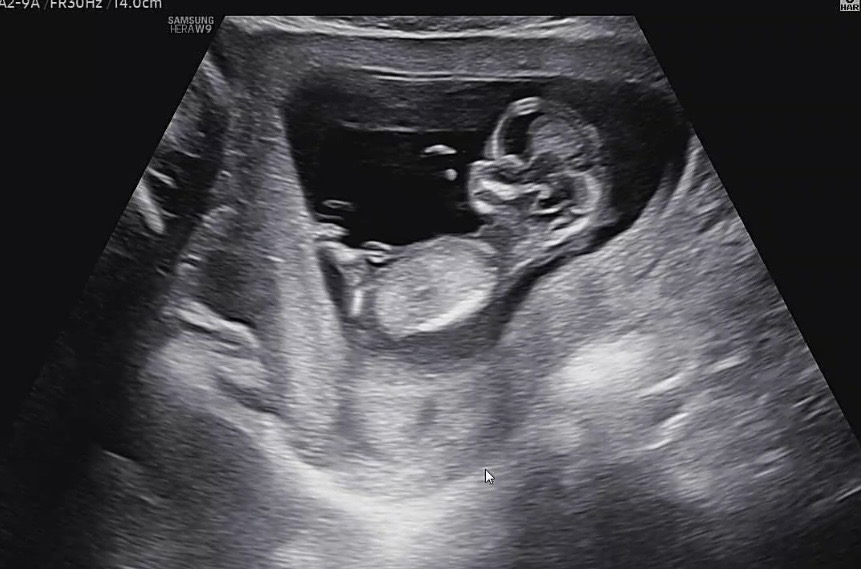

12주 4일차 각도법 궁금해요 ㅎㅎㅎ

다리를 접고 있어서 그런지 제 눈엔 하나도 안보여서 .. 각도법 고수님들 계신가요 ?!! ㅜㅜ + 댓글에 사진 하나 더 첨부했습니당 :)

다른 사진도 한장 더 남깁니다 !!